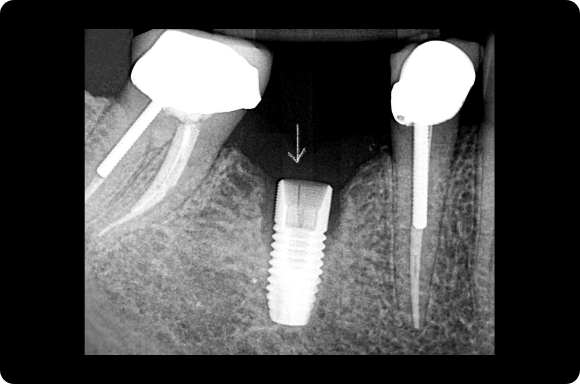

Ce cours de niveau maîtrise aborde à la fois la prévention et la gestion des complications chirurgicales et restauratrices. Dans le domaine chirurgical, la présentation se concentre sur l’échec précoce de l’implant et la maladie péri-implantaire ultérieure. Les concepts prothétiques comprendront la conception de prothèses préventives, le retrait des vis/piliers et un séquençage qui reconnaît l’importance de l’expérience du patient.